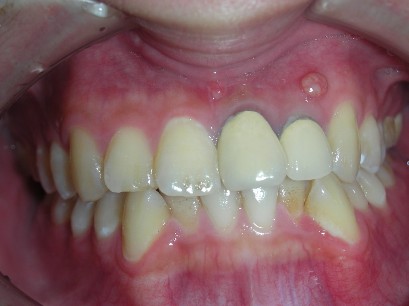

全瓷冠-門齒區根尖囊腫

審美牙科

全瓷冠